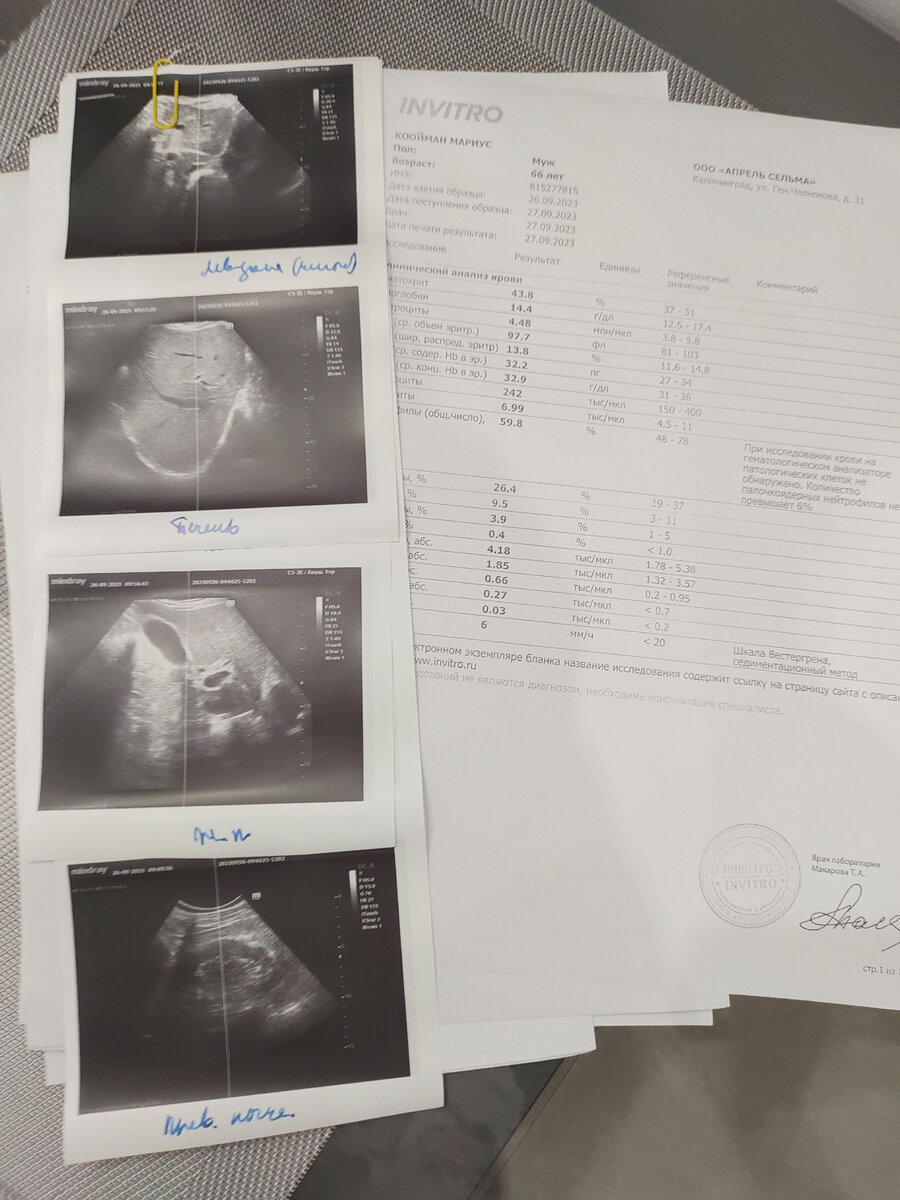

В Калининграде обследовали все внутренние органы, сделали все анализы крови, мочи и сегодня мы пришли на прием к врачу. Доктор достала пухленькую стопочку листочков с результатами и стала рассказывать. Анализы хорошие, никаких опухолей нигде нет, все органы для его возраста нормальные, кроме одной почки. В которой есть маленькие два камушка.

Видимо когда он доставал велик, то напрягся и камушки сдвинулись. Теперь камушки хаотично мотыляются по почке, то закупорят что-то там ( я забыла что), то освободят проход. Поэтому и боли пару дней невыносимые, пару дней более -менее. Камешки маленькие, оперативного вмешательства не требуют.

К слову, многие мне говорили, что к врачам в России только попади, особенно в частной клинике, тут же найдут кучу несуществующих болячек и навыписывают медикаментов только успевай платить. Доктор сказала, что проблема только в почке. Выписала испанский препарат, который растворяет камни и для обезболивания выписала уколы "Баралгина". Всё.